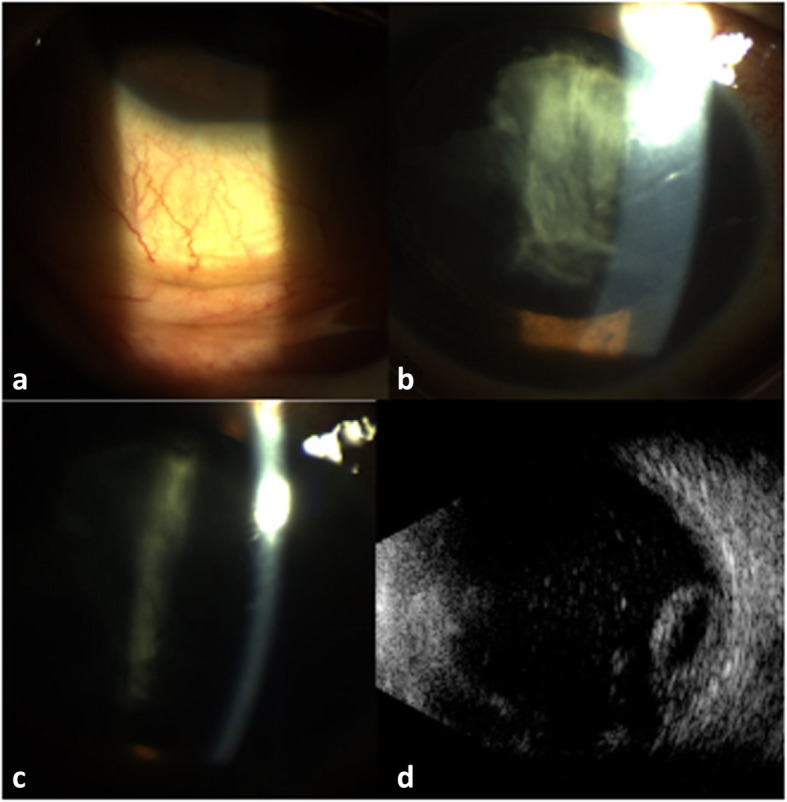

Fig. 1.

(a) Slit-lamp photography seven days after pars plana vitrectomy showing a mild conjunctival hyperemia and hypopyon. (b,c) Three days after initiation of topical steroid therapy, the hypopyon has resolved. Note the lack of typical lens capsule convexity and the residual cortical material adherent to the anterior lens capsule. (d) B-scan ultrasonography shows a globular echogenic structure in the inferior posterior vitreous cavity resting on the retina consistent with a dislocated lens nucleus

The following day, ophthalmic examination was unremarkable as the patient had positive light perception with a quiet anterior chamber, and an intra-ocular pressure (IOP) of 23 mmHg. The lens examination showed a subcapsular posterior cataract. The retina was flat posterior to the bubble. The patient was discharged on day one post-operatively and topical corticosteroid and antibiotics were prescribed. Seven days later, he presented with sudden photophobia, mild eye pain and hyperemia. On ophthalmic examination, the visual acuity was limited to positive light perception with mild corneal edema, and the IOP was 30 mmHg. A slight hypopyon was noted inferiorly with a fibrinous exudate (Fig. 1a). Posterior segment evaluation was hindered by the anterior segment inflammation. B-scan ultrasonography did not provide reliable information due to the presence of the remaining intravitreal gas bubble.

The patient was treated with topical mydriatics and topical and oral corticosteroids (prednisolone, 60 mg/day). On day ten post-operatively, the anterior segment inflammation had resolved and good pupillary dilation was obtained revealing centrally clouded anterior capsule with absence of nucleus (Figs. 1 b and c). Fundus examination was obscured by opacifications behind the anterior lens capsule representing swollen lens cortex material. B-scan ultrasonography revealed a globular echogenic structure in the inferior posterior vitreous cavity resting on the retina corresponding to a dislocated lens nucleus (Fig. 1d). The diagnosis of posterior nucleus dislocation with lens-induced uveitis was then retained.